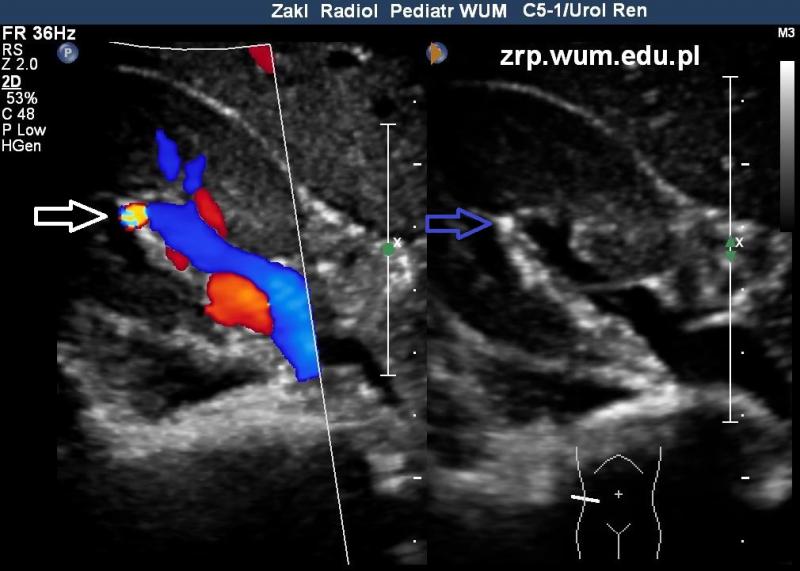

Rozpoznanie: W badaniu USG uwidoczniono złóg (niebieska strzałka) w kielichu grupy środkowej nerki prawej. Widoczny artefakt migotania (artefakt świetlika, ang. twinkling artifact) (biała strzałka), który można wykorzystać do potwierdzenia obecności i lokalizacji złogu.